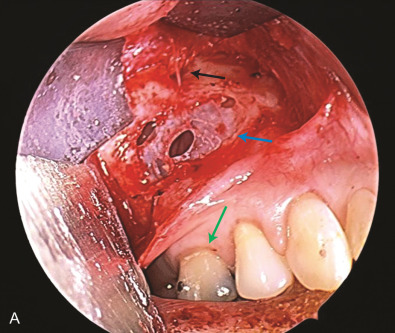

The maxillary division carries sensory information from the lower eyelid, cheek, upper lip, upper teeth, and associated mucosa. The zygomatic nerve gives its terminal branch as the zygomaticofacial nerve that supplies sensation to the lateral cheek and portions of the forehead. The terminal branch of the maxillary nerve exits the facial skeleton as the infraorbital nerve. This nerve is encountered regularly in midface injuries as well as orbital floor fractures ( Fig. 3.16.3 ). The mandibular division is the largest branch of the trigeminal nerve. Before the mandibular nerve enters the medial mandible at the lingula, it will bifurcate and the lingual branch will course within the soft tissue of the floor of the mouth, where it will be in intimate association with the submandibular duct. The terminal branch of the mandibular nerve will enter the medial mandible within the inferior alveolar canal and exit at the mental foramen to give sensation to the mandibular dentition, mucosa, and lower lip. Both of these nerves can be encountered in mandibular fractures as well as soft tissue injuries to the submandibular region ( Fig. 3.16.4 ).